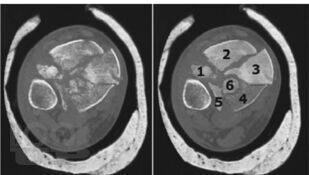

Данное учебное пособие содержит подробное описание диагностики и тактики лечения переломов дистального метаэпифиза большеберцовой кости и возможности применения внеочагового и накостного методов лечения при данных видах переломов, а также описание послеоперационного ведения больных с данной патологией, возможные осложнения и сроки реабилитации после этого вида травмы.